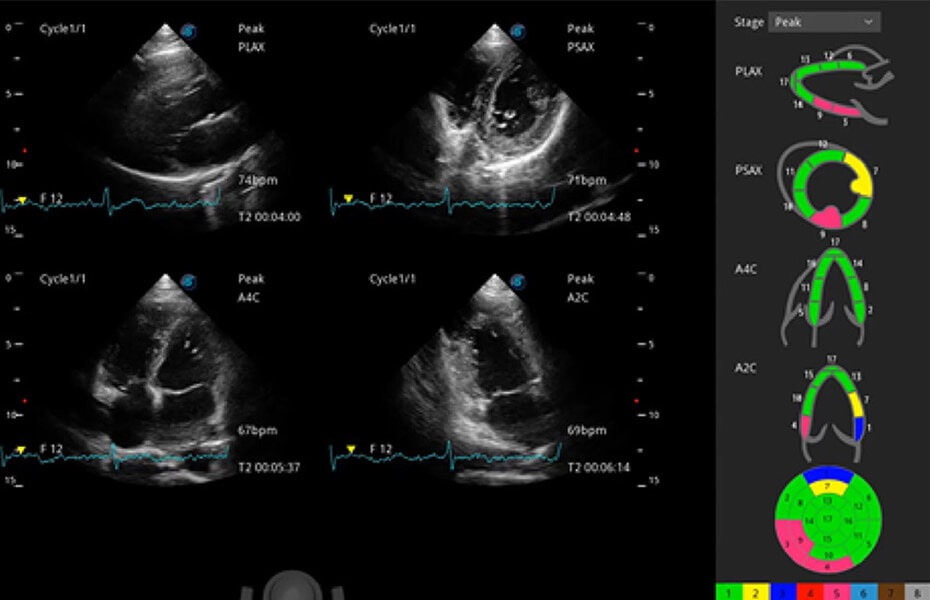

ProPet 60 作为一款高端台式动物超声设备,为动物医生的日常诊断提供了一系列贴合动物临床需求、解决临床实际问题的高级成像功能。凭借全系列高清探头,满足医生对腹部、心脏、生殖、浅表、肌骨等成像的所有需求,切实帮助您提升检查效率,提高诊断信心。

动物是人类最亲密的朋友和最值得信赖的伙伴。开立医疗也一直致力于探索动物专用的超声影像解决方案。 全新推出的ProPet系列,是开立在动物超声影像智能化、专业化、精准化的一次跨越式革新。动物不能用言语来表述自己的不适,通过超声影像,ProPet系列搭建了动物医生与不同物种沟通的“桥梁”,为动物医生注入了“治愈之力”。